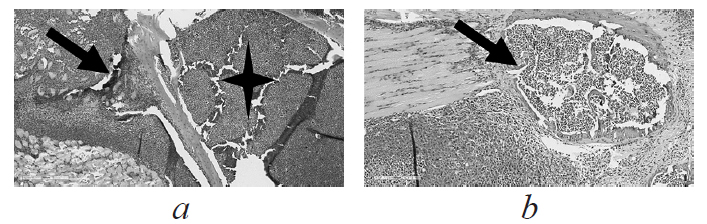

RESULTS: Tumor was developed at the site of primary transplantation in all mice from groups 3 and 4, which was confirmed by visual assessment and the results of histological examination. Tumor growth in the main group was significantly less than in the control group of the tumor, which may be due to intoxication against the background of tuberculosis infection. All infected mice from groups 2 and 4 developed pulmonary tuberculosis, confirmed by computed tomography of the lungs, bacteriological and histological examination of lung samples. Mycobacterial load in the lungs was the highest in animals with concomitant pathology of tuberculosis and tumor. The survival rate of mice was determined to a large extent by tumor growth rather than by the progression of tuberculosis infection.